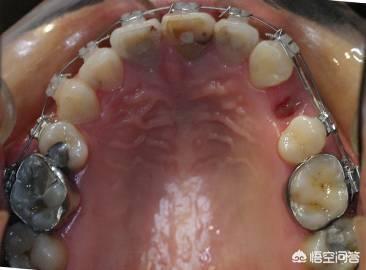

而获取间隙的方法无外乎是减数(拔牙)、减径(片切牙缝)、扩弓(扩展狭窄的牙弓)此外还有推磨牙向后。

具体采用何种方式获取间隙则需要正畸医生通过X光片测量诊断后才能制定方案。

(图片来源于网络)